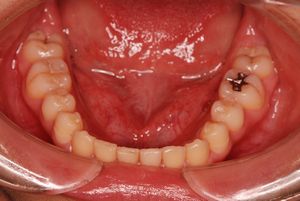

治療前 の 下アゴ です 動く矢印治療後 の 下アゴ です